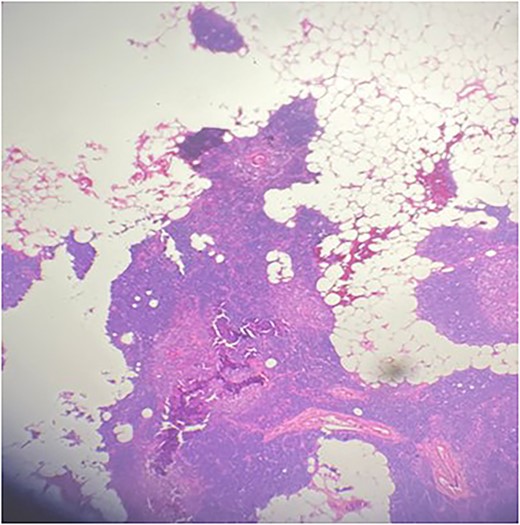

A 36-year-old male with a history of end-stage renal disease (because of polycystic kidney disease) on dialysis, for which he is on paricalcitol and sevelamer, and total parathyroidectomy with autotransplantation in the left forearm performed in 2011 for secondary hyperparathyroidism presented with generalized bone pain. Heart rate was 114 bpm, respiratory rate was 18 breaths/min, oxygen saturation was 96% and blood pressure was 136/72 mmHg. Laboratory investigations were ordered and revealed high PTH (>1300 pg per ml), low calcium (2.7 mg per dl) and low phosphate (1.8 mg per dl). A sestamibi scan was ordered and revealed hyperactive parathyroid tissue in the upper retrosternal area (Fig. 1). Removal of the ectopic parathyroid tissue was planned; however, the lesion was not localizable intraoperatively, and further chest CT with preoperative coil localization was performed, which revealed a retrosternal ectopic parathyroid tissue anterior to the ascending aorta (Fig. 2).Right thoracoscopy using fluoroscopy for ectopic parathyroid removal and lymph node biopsy was performed, and the specimens were sent to histopathology, which showed multiple nodules of parathyroid tissue with benign lymph nodes (Figs 3 and 4). A final diagnosis of parathyromatosis was made. The patient was discharged in good condition without complaints of bone pain. Upon 2-week follow-up, the patient was symptom-free and laboratory investigations revealed phosphate of 2.1 mg per dl, calcium of 2.4 mg per dl and an elevated PTH of 350 pg per ml, for which a sestamibi scan was performed and showed no evidence of uptake in the neck and mediastinum but revealed uptake in the left forearm from the previous autotransplantation.

Multiple nodules of hypercellular parathyroid tissue within unremarkable thymic tissue.